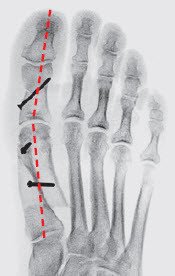

Ziel der Chirurgie ist die möglichst exakte Wiederherstellung einer normalen Anatomie, wie sie vor dem Auftreten der Deformität bestanden hat. Der schräg stehende Mittelfussknochen, der nach innen drückt, muss also aufgerichtet und in der korrekten Stellung stabilisiert werden. Die Grosszehe steht dann wieder gerade auf dem Mittelfussknochen und entfaltet ihre volle Stützfunktion, was die Überlastungsschmerzen an der Fusssohle zum Verschwinden bringt. Das bei uns am häufigsten angewandte Operationsverfahren ist die sogenannte «Scarf»-Osteotomie, die hier dargestellt wird. Diese Korrektur erfolgt durch einen Knochenschnitt (Osteotomie), der mit zwei bis drei kleinen Schrauben in der korrekten Stellung bis zur Heilung (sechs bis acht Wochen) fixiert wird. Die später funktionslos gewordenen Schrauben spürt man nicht, sie müssen nur ausnahmsweise entfernt werden.

Durch diese Fehlstellung verliert die Grosszehe einen Teil ihrer wichtigen Stützfunktion und der benachbarte zweite Mittelfussknochen (Abbildung 2) wird chronisch überbelastet. Die Überlastung zeigt sich in der häufig beobachteten, schmerzhaften Hornhautverdickung unterhalb des zweiten (oft auch dritten) Mittelfussköpfchens. Die dort stark strapazierten Bänder und die Gelenkkapsel der zweiten (und dritten) Zehe können einreissen, sodass die Zehe keinen Halt mehr hat und sich eine Hammerzehe bildet (Abbildung 3).